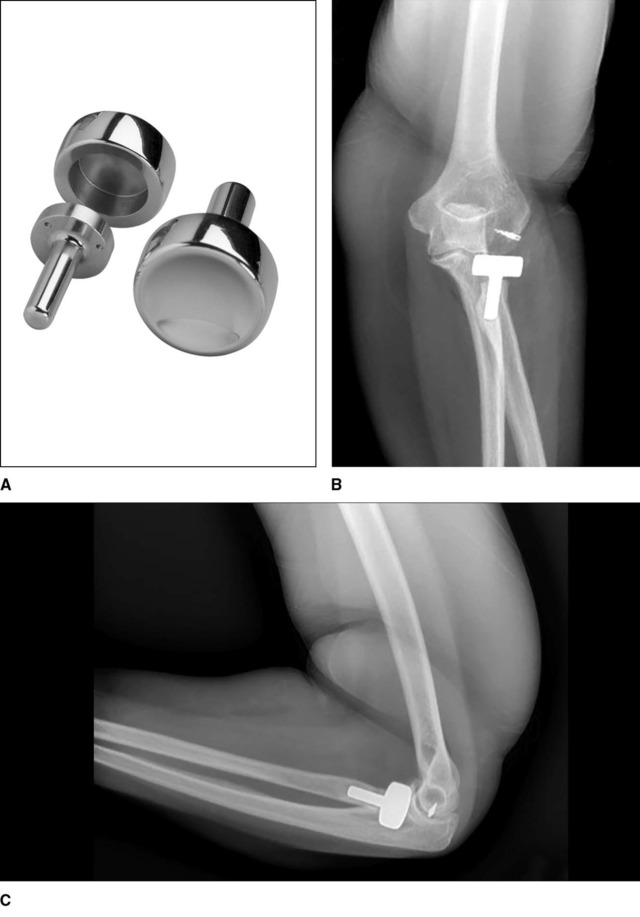

肱桡关节置换

肱桡关节置换是一个相对较新的手术方法,可被用于肱桡关节炎、不可重建的肱骨小头骨折以及肱骨小头坏死(见图 9)。肱骨小头假体有带柄和不带柄两种。将肱骨小头假体置换与之前讨论的桡骨头假体置换联合起来就构成了肱桡关节置换。对于存在肱桡关节炎的患者,单纯的桡骨头关节置换可能会进一步影响已经存在退变的肱骨小头。

目前只有一例肱桡关节置换的文献报道,Heijink 等人使用肱桡关节置换治疗了 3 例合并肱骨小头退变的 Essex-Lopresti 损伤患者。3 例患者的疼痛和功能情况均获得改善,但是有 1 例患者因为假体松动而需要进行翻修手术。由于目前只有这一篇关于肱桡关节置换的病例报道,今后需要进行进一步的临床和生物力学研究来证实该技术是否存在优势。

图 9 肱桡关节假体。该假体包括肱骨小头假体和压配式的桡骨头假体